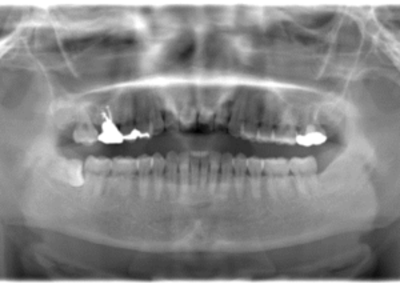

初診時レントゲン(パノラマ)

初診時パノラマX線写真と口腔内写真。

抜歯予定の歯と移植予定の歯

右上6抜歯後

右上6(青丸)を抜歯し、右下8(赤丸)を移植することを計画した。

右上の抜歯後の治癒を待つため、抜歯の1ヶ月後に移植を行うこととした。